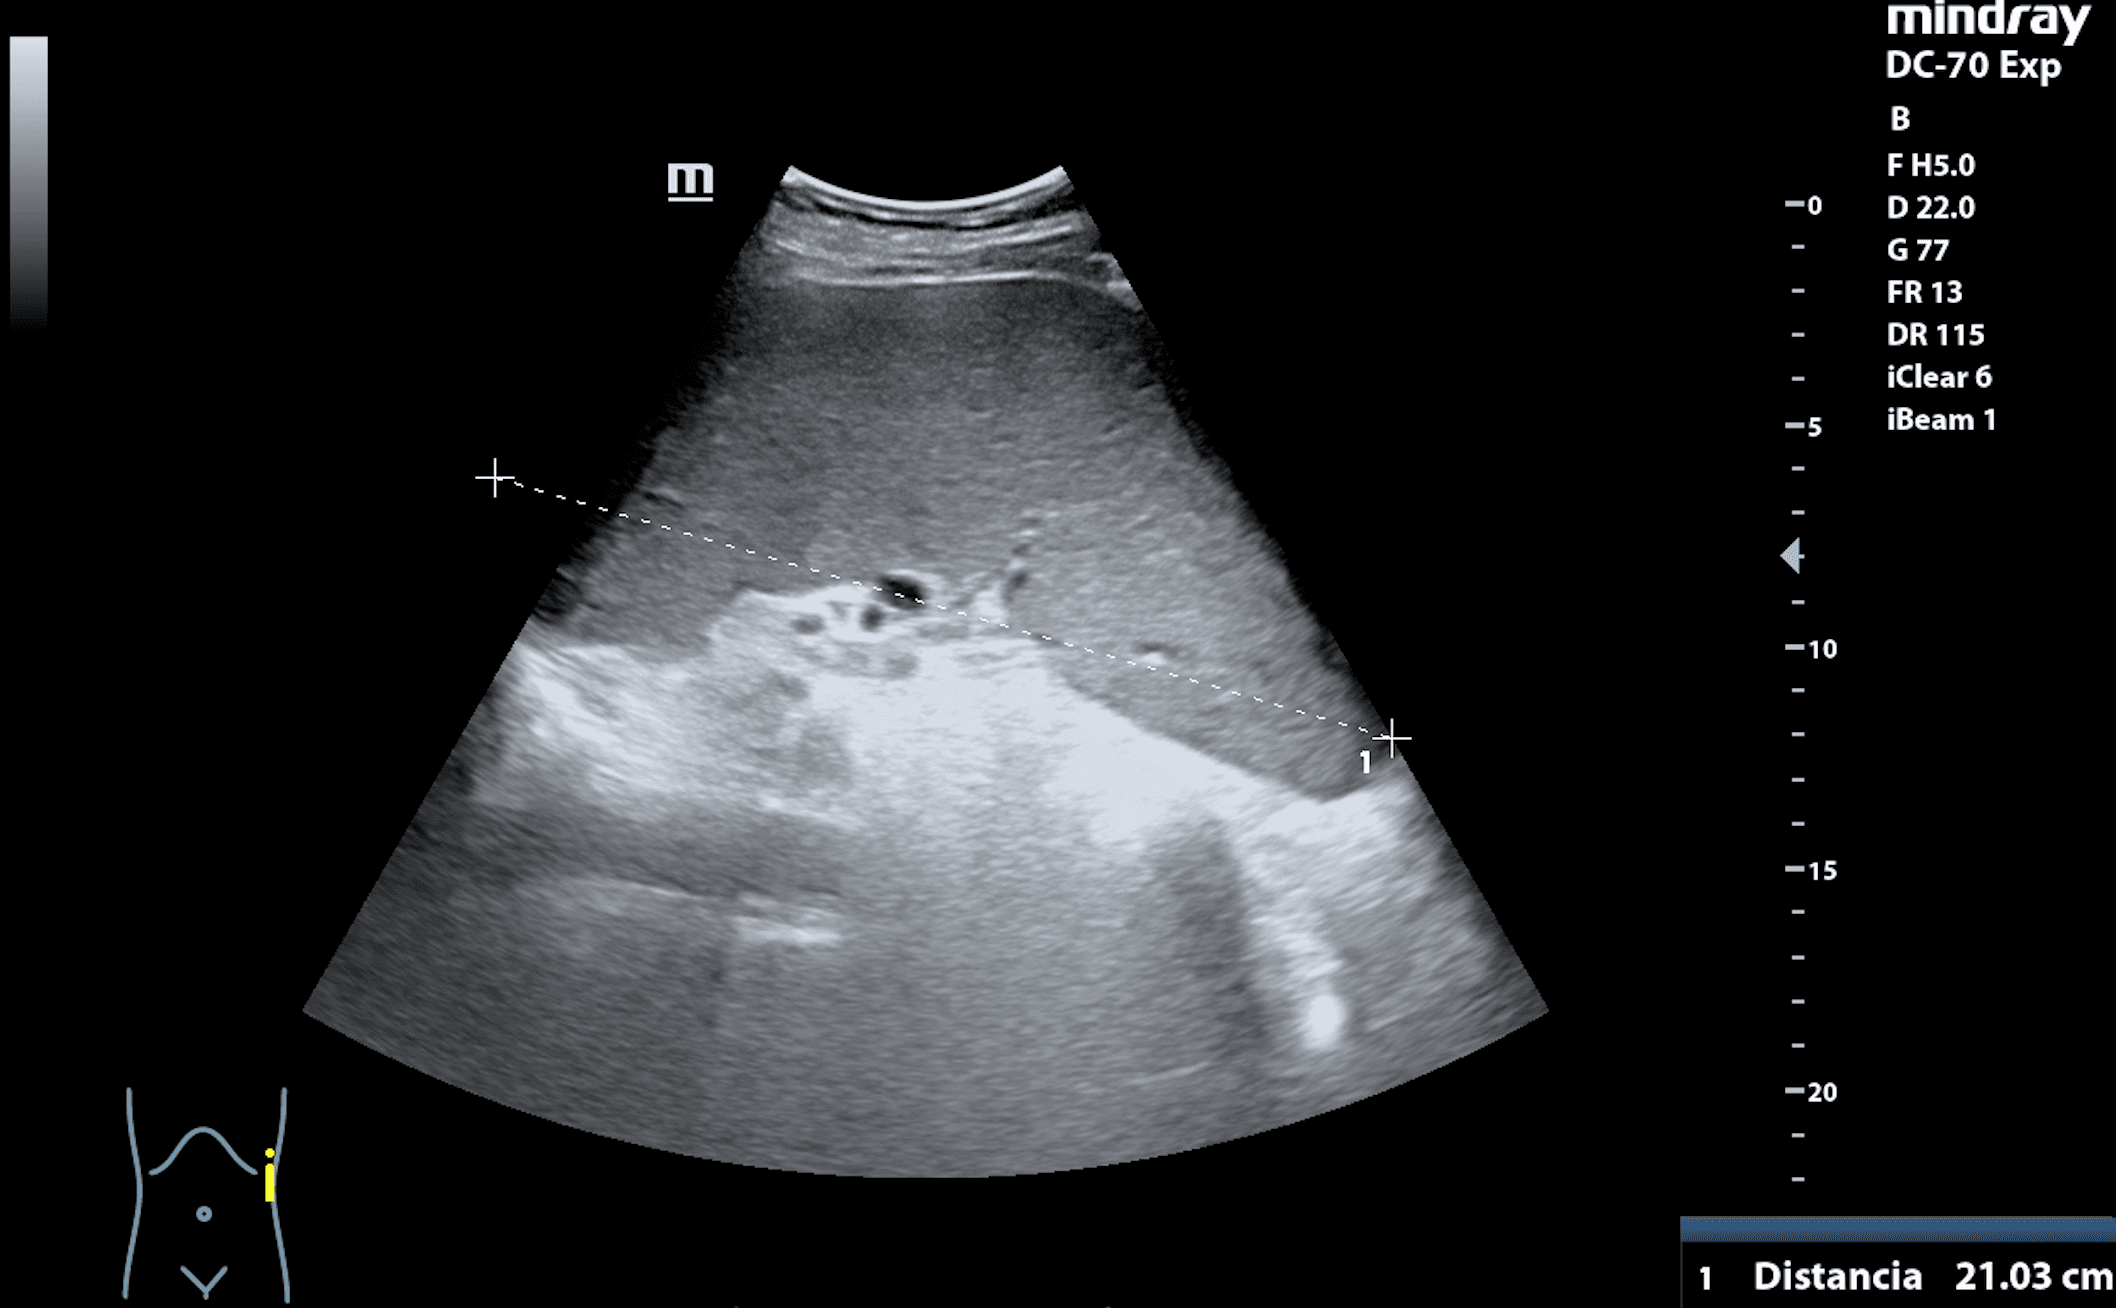

Hallazgos ecográficos

Hepatomegalia y esplenomegalia de 21,03 cm. Adenopatías retroperitoneales.